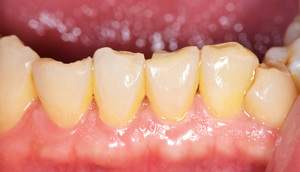

歯石除去

治療前

治療後

| 年齢 | 25歳・男性 |

| 主訴 | 歯石をとりたい・検診 |

| 治療内容 | 各種検査・歯石除去 |

| 治療期間 | 60分 |

| 費用 | 初診料3,000〜4,000円前後 +歯石除去約1,000円 |

| リスク・副作用 | ・処置後に歯がしみることがあります。 ・歯と歯の間に隙間ができるので、息が漏れ発音しにくいと感じることがあります。 ・歯ぐきの炎症が軽減すると歯ぐきが引き締まり、歯が長く見えることがあります。 |

| 担当者所見 | 前歯の裏側にすぐに歯石が溜まってしまいザラザラして気になるとご相談いただいたので適切な歯ブラシの当て方とフロスの通し方をお伝えさせて頂きました。 |